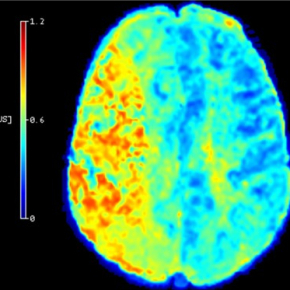

Une équipe du Centre de recherche en acquisition et traitement de l'image pour la santé a développé une méthode qui permet, à partir des images d'IRM de patients ayant subi un AVC d’améliorer l’évaluation des zones du cerveau pouvant récupérer après un traitement de reperfusion. Ces résultats, qui ouvrent la voie à une meilleure prise en charge des patients, en particulier de ceux jugés parfois inéligibles à ce genre de traitement, sont publiés dans la revue Stroke.